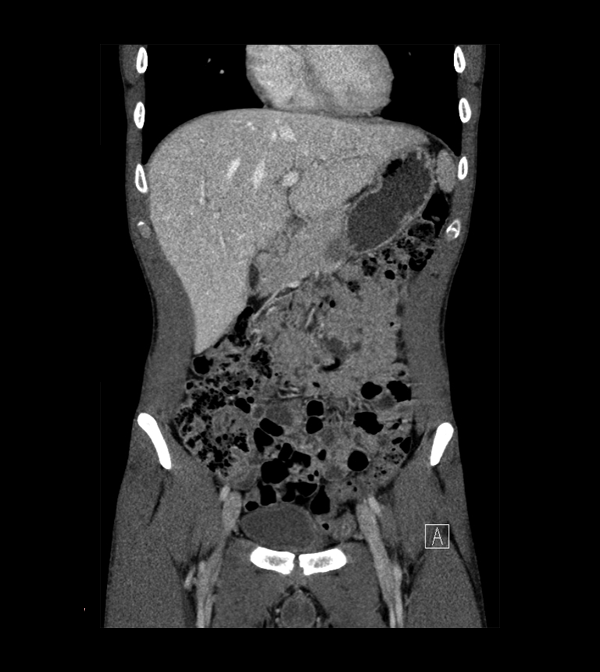

Body

Covers abdominal CT anatomy.